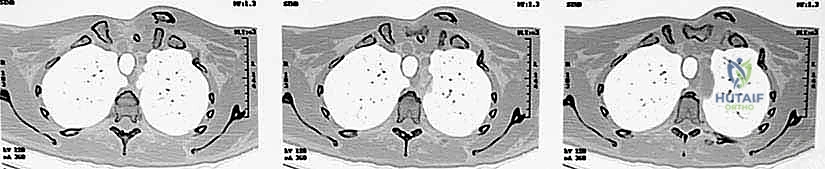

- التصوير المقطعي المحوسب (CT Scan) - المعيار الذهبي: يؤكد الدكتور هطيف أن الأشعة المقطعية، خاصة مع إعادة البناء ثلاثي الأبعاد (3D Reconstruction)، هي الإجراء الحاسم. فهي تحدد بدقة متناهية اتجاه الخلع، وجود كسور مصاحبة، ومدى قرب الترقوة من الهياكل الحيوية.